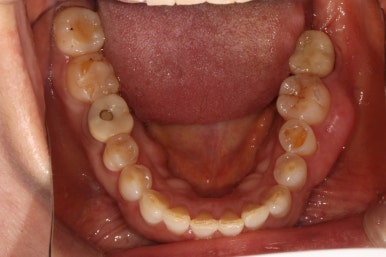

왼쪽: 위턱, 오른쪽: 아래턱

위턱과 아래턱의 교합면 사진입니다.

아래턱 사진을 보시면 치아가 하나 비어있는 것을 아실 수 있죠? 두 개 비어보이시겠지만, 하나는 사랑니니깐 한개로 칩니다. 아까 치과용 파노라마에서 빨간색 동그라미!

위턱 사진을 보시면 뿌리만 있는 치아를 확인하실 수 있을거에요. 노란색 동그라미!

마지막으로 딱 한개 있는 금니를 보실 수 있을텐데, 이차 충치가 있어 다시 치료해야했던 치아입니다. 파란색 동그라미!